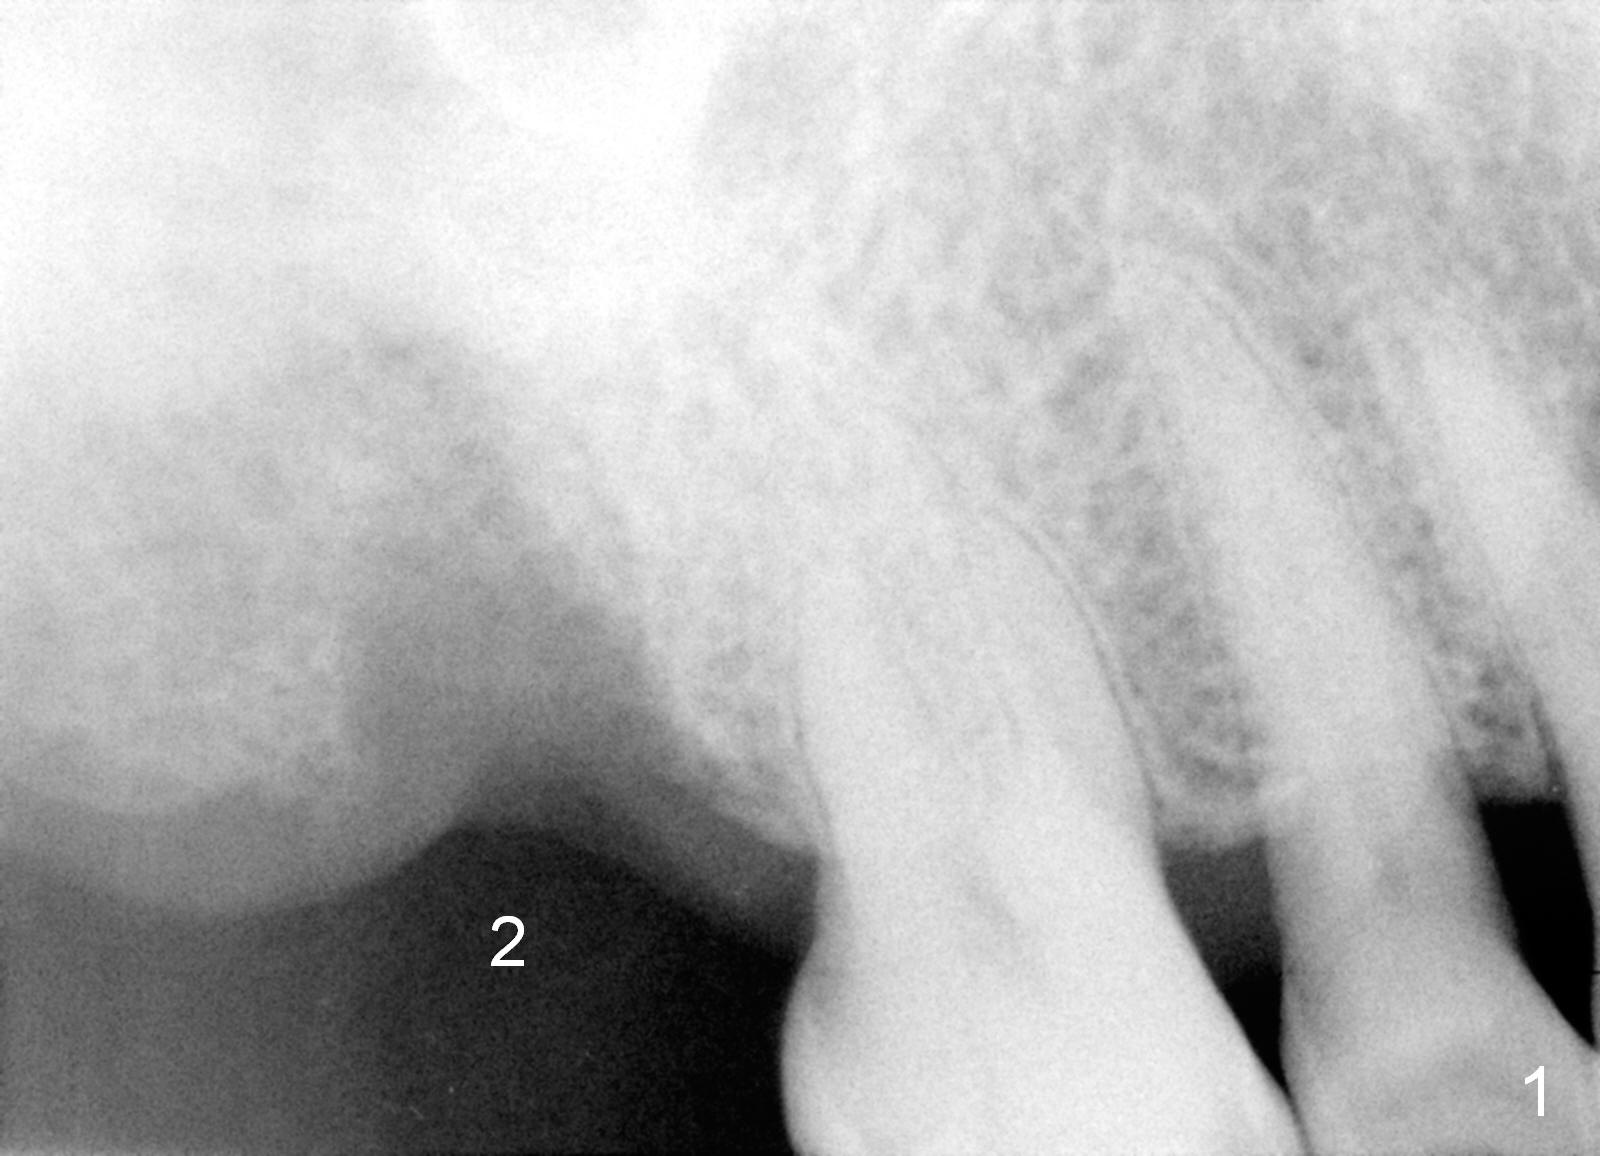

A 76-year-old man had the tooth #2 extracted (due to endo failure) 2 weeks ago (Fig.1). The socket looks "empty" (Fig.2 S, basis for osteotomes). It consists of the buccal (pink dashed line) and palatal (red) ones (Fig.3). In one word, the socket is pyramidal. It appears that a tapered implant is appropriate for the site. Clinically, the socket is healing with soft tissue covering the opening of the socket.